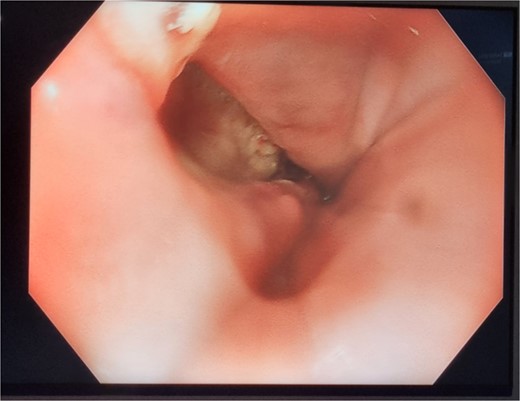

The patient was treated with antibiotics and VACStent insertions, requiring two stent placements (Fig. 1a). By the second stent removal, the anastomotic leak had closed (Fig. 1b). He experienced an episode of acute kidney injury managed with fluids. By postoperative day 24, the leak had resolved, the stent and porta Cath were removed, and the patient was discharged with normal blood results and a follow-up scheduled. The patient continued to manage his overall health with regular follow-ups.

Patient One: (a) Before VACStent insertion, showing the oesophageal defect. (b) After VACStent treatment, demonstrating successful defect closure.